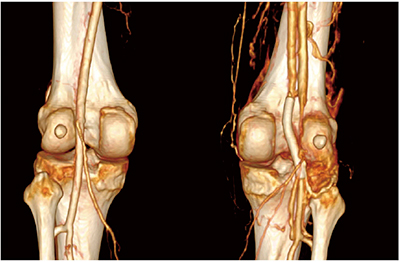

Case1では,70kVのLow kVイメージングにより造影剤量をさらに低減できた。20mLの造影剤を生理食塩水で50%希釈して使用したが,頸動脈および総腸骨動脈内の十分な造影効果が得られている(図1)。

図1 Case1:Low kVイメージングによる造影剤量の低減

(Whole-Body CT,70kV,造影剤量20mL)